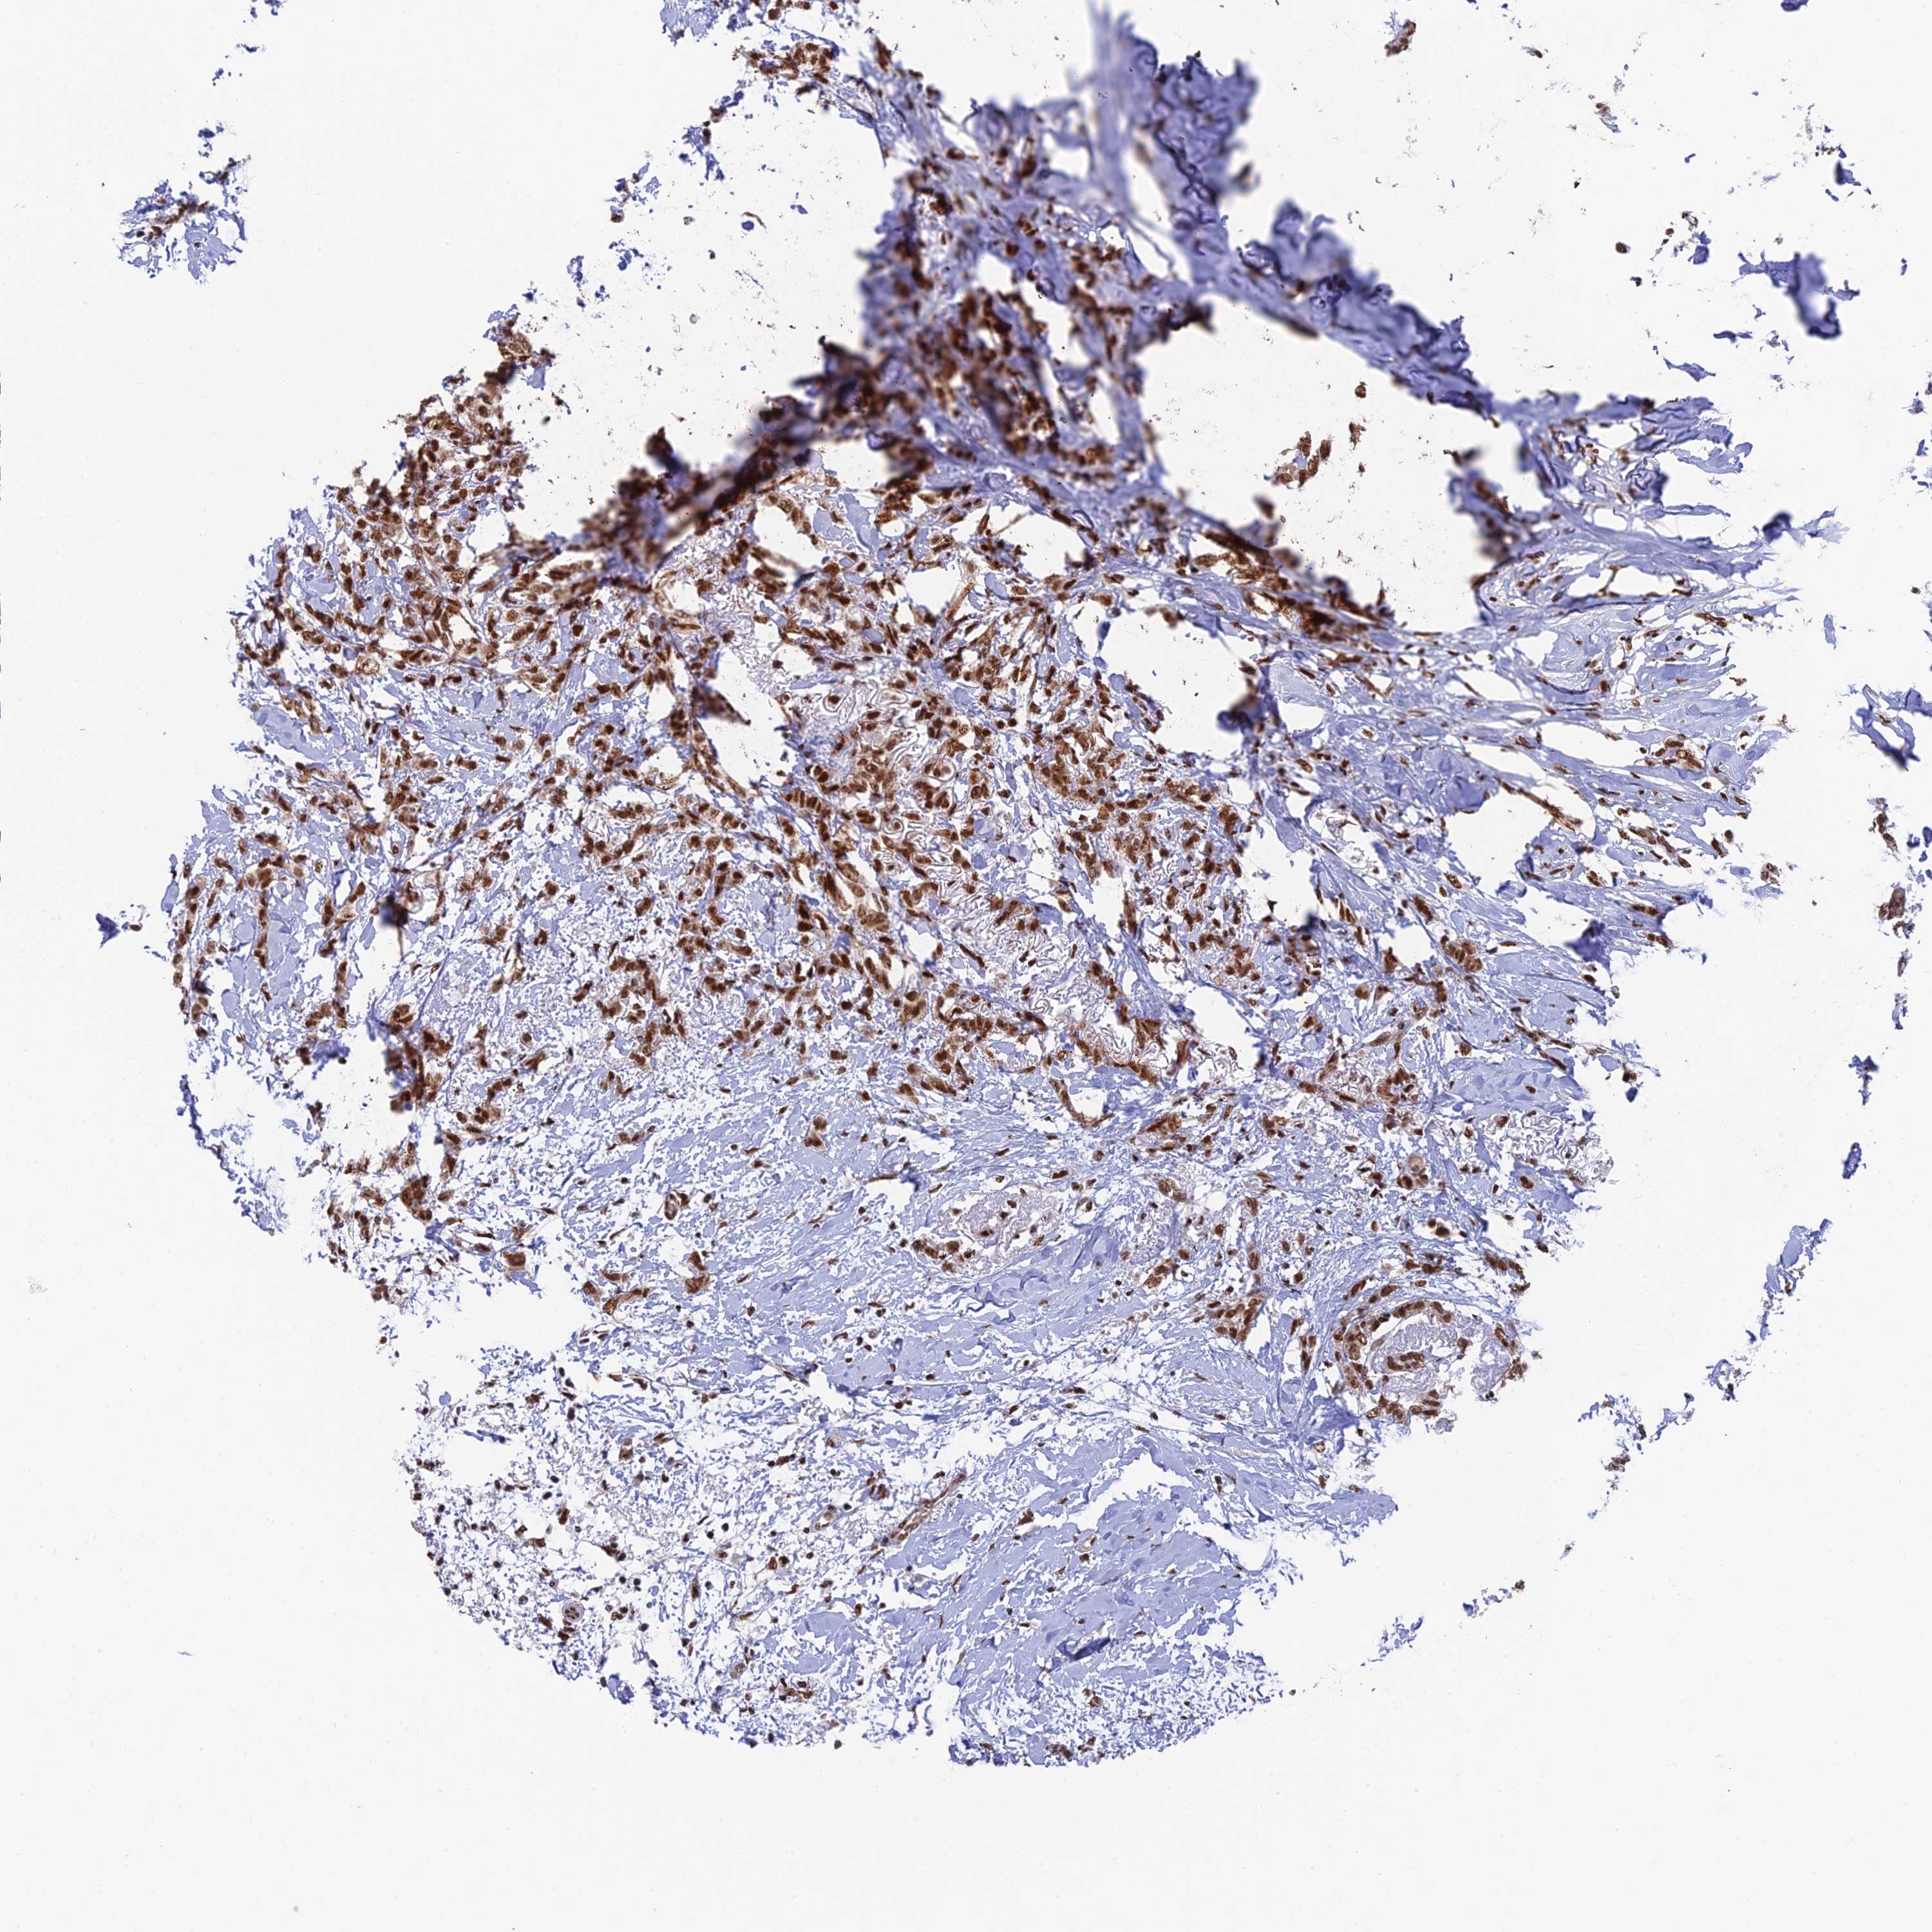

BRCA TCGA BRCA VALIDATION PROTEIN EXPRESSION

ANTIBODIES

AND

VALIDATION